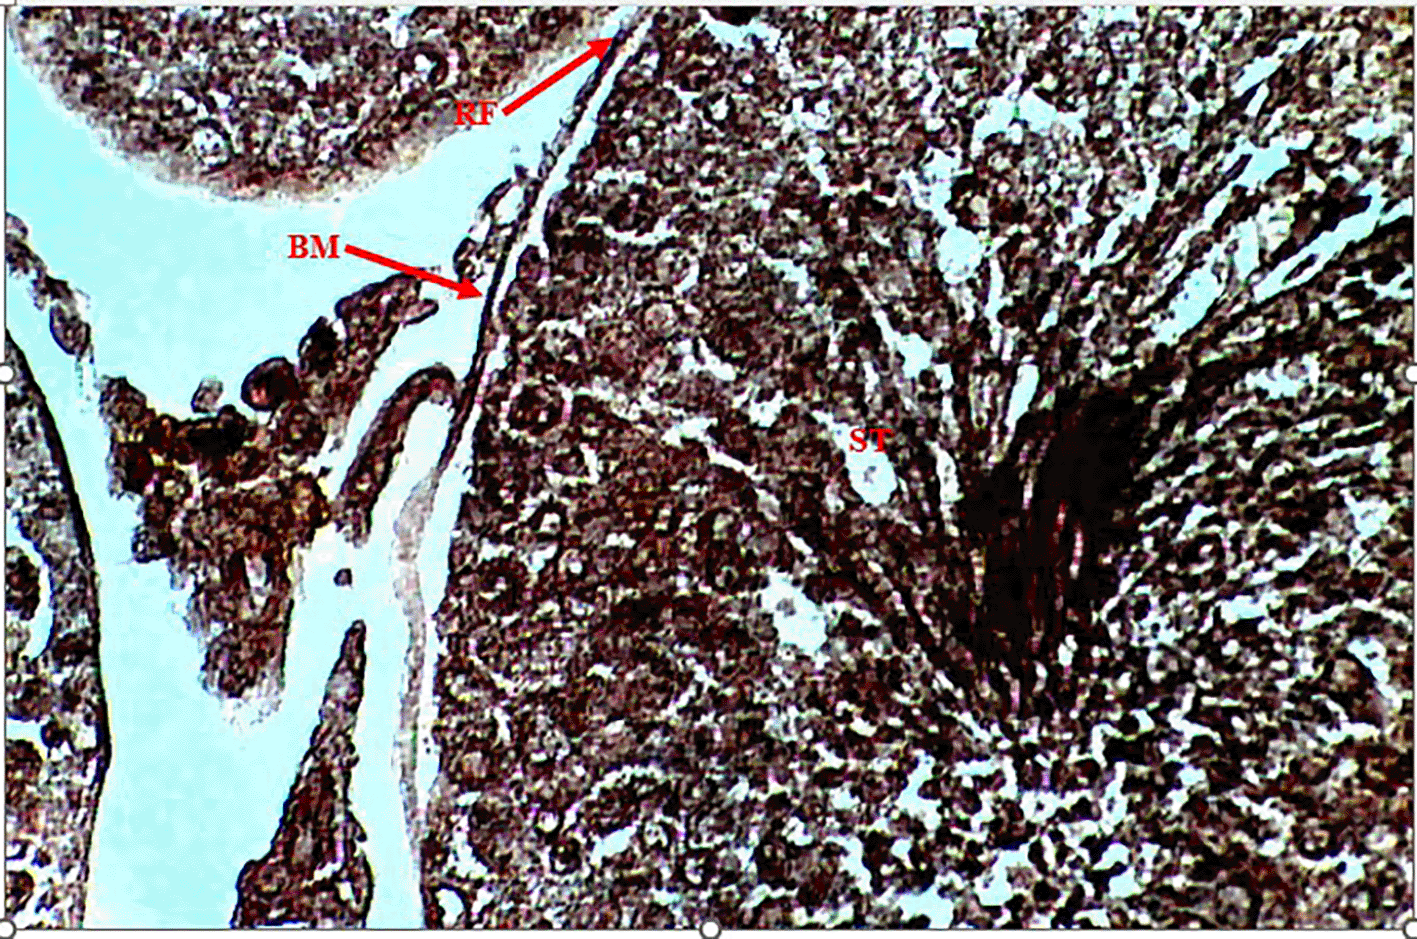

Methenamine Silver (Gomori PAM) staining of testicular tissue in the Control Group (Group 1) revealed moderate reticular fibre expression with intact basement membranes and minimal formation around seminiferous tubules (Figure 1), indicative of normal testicular architecture. In contrast, the Methamphetamine-Only Group (Group 2) exhibited markedly increased reticular fibre density, characterized by thickened fibres encircling the basement membrane of seminiferous tubules (Figure 2), suggesting methamphetamine-induced structural alterations. The Low Dose Group (Group 3), treated with methamphetamine and 100 mg/kg b.w. C. longa, demonstrated moderate reticular fibre expression with preserved basement membrane integrity (Figure 3), indicating partial attenuation of drug-induced changes. Further reduction in fibre density was observed in the Medium Dose Group (Group 4), where reticular fibre formation around tubules decreased significantly compared to Group 2 (Figure 4). Notably, the High Dose Group (Group 5) showed the most pronounced protective effect, with sparse reticular fibre expression and intact basement membranes resembling near-normal morphology (Figure 5).

Photomicrograph testes showing moderate expression of reticular fibers (RF). Intact basement membrane (BM) and decreased formation of reticular fiber around the seminiferous tubules (ST).